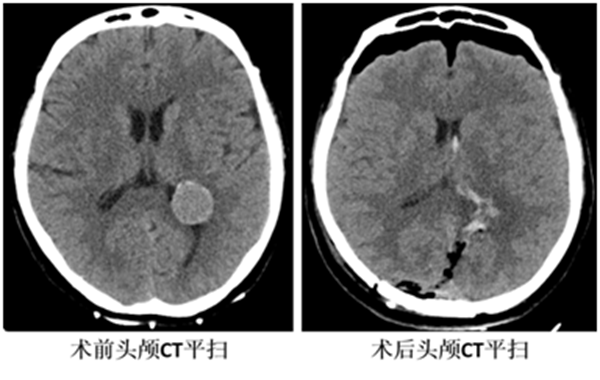

仔細的術(shù)前檢查及評估后,神經(jīng)外科全內(nèi)鏡手術(shù)團隊開展了病例討論,大家一致認同后枕部直切口,全神經(jīng)內(nèi)鏡下經(jīng)對側(cè)后縱裂-大腦鐮-楔前葉入路切除左側(cè)腦室三角區(qū)腦膜瘤這一手術(shù)策略。謝主任解釋,該手術(shù)方案的特點在于:1、充分利用了重力導(dǎo)致腦組織的自然塌陷;2、充分利用了后縱裂的自然腔隙;3、充分利用了楔前葉這一功能啞區(qū);4、充分利用了對側(cè)入路,使得手術(shù)操作角度更為直接?;谶@4個特點,讓這一深部手術(shù)從切口到腫瘤切除均能實現(xiàn)最大化的微創(chuàng)。

1月31日,在手術(shù)室護士、麻醉醫(yī)師的全力配合下,謝主任帶領(lǐng)團隊為崔阿姨實施了全內(nèi)鏡下全切腫瘤。術(shù)后視覺功能完好,也沒有出現(xiàn)語言、肢體運動等其它神經(jīng)功能障礙,崔阿姨一家對手術(shù)效果非常滿意。